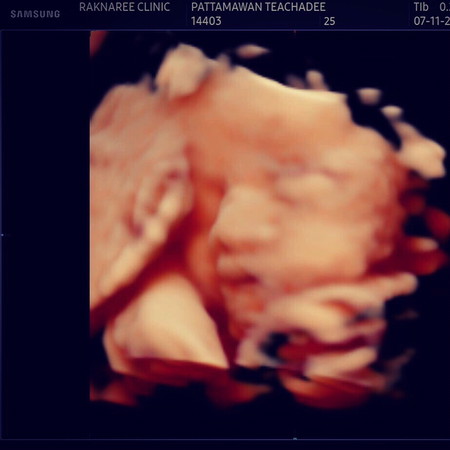

รูปซาวด์4มิติแบบนี้ถือว่าชัดมั้ยค่ะ. ถ้าออกมาแบบนี้จริง จะปลื้มมมากจมูกมาไกลมาก. ครบ32 แม่ก็ดีใจมาก อีก7week2day ก็จะคลอดแล้ววว

ลูกบ้านนี้ตอนซาวด์ก็โด่งคะออกมาก็ไม่ค่อยเท่าไหร่